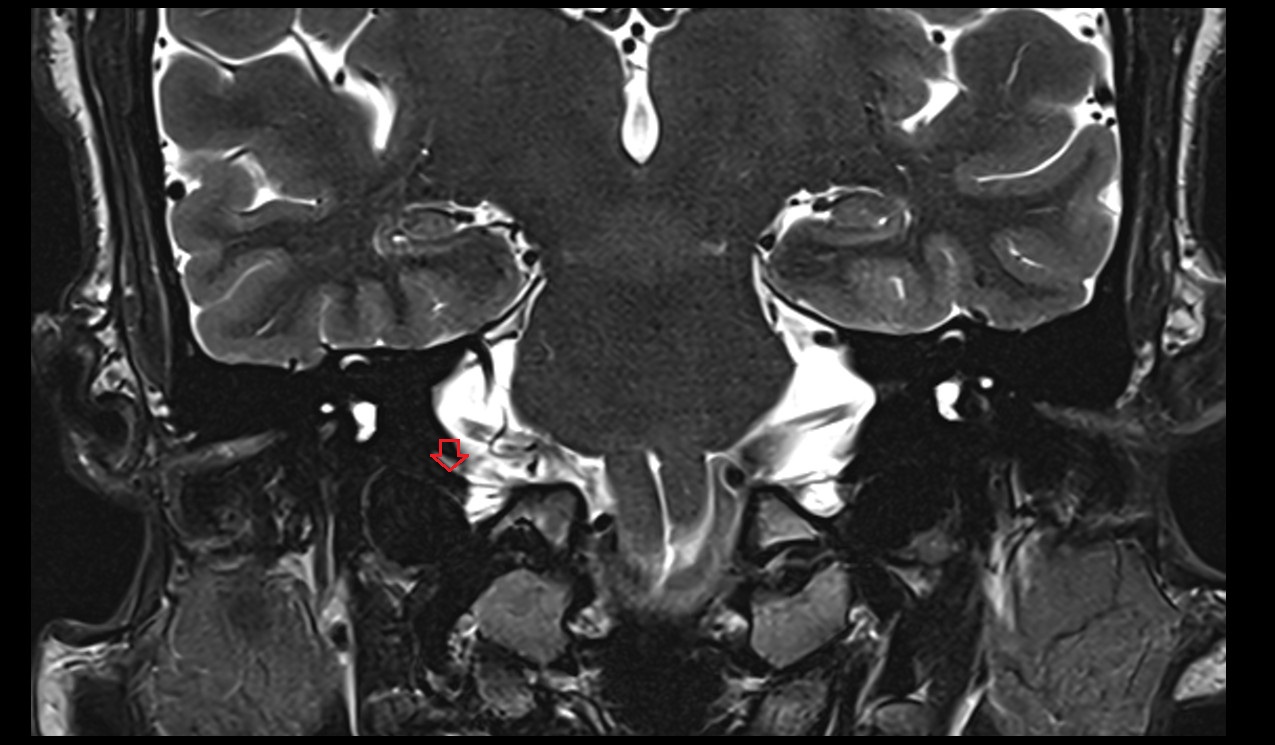

- Temporomandibular joint

- Mandibular condyle

- Mandibular fossa

- Articular disc of temporomandibular joint

- Articular eminence